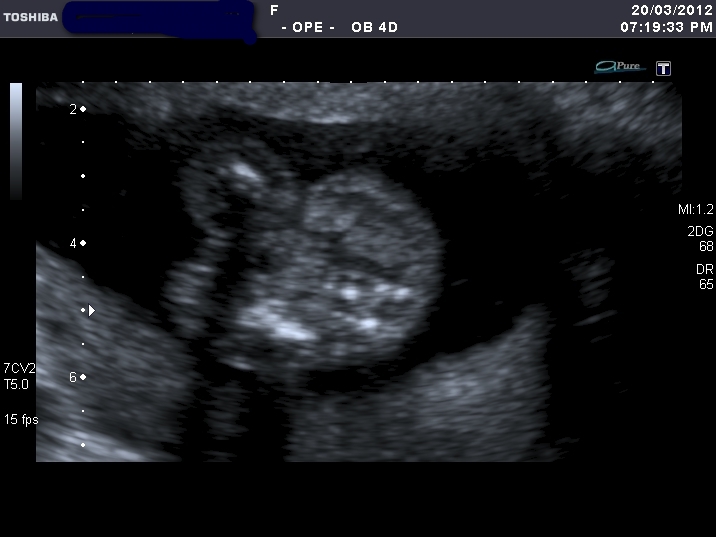

I'm clueless what these represent, perhaps one is potty shot? If so, enlighten me where to look!lol

Attachment 1798 Attachment 1799Attachment 1800 Attachment 1801